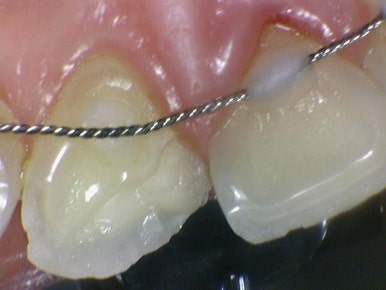

일단 원래 계획은 왼쪽은 금만 가있는 정도라서 많이 깨진 오른쪽 치아만 라미네이트를 하는 것이었는데요,

크라운과 라미네이트 중 라미네이트를 하기로 한 이유는 오른쪽 사진처럼

치아 뒤쪽에 교정이 끝나고 유지장치가 붙어있는 상태였기 때문에 크라운을 하는 경우 크라운에 유지장치가 잘 붙지 않을 뿐더러, 크라운을 하면 크라운을 하고 다시 새로운 유지장치를 재제작해야하기 떄문에

유지장치가 있는 부위는 크게 건드리지 않고 치아 앞쪽만 처리해서 붙일 수 있는 라미네이트를 하기로 하였습니다.